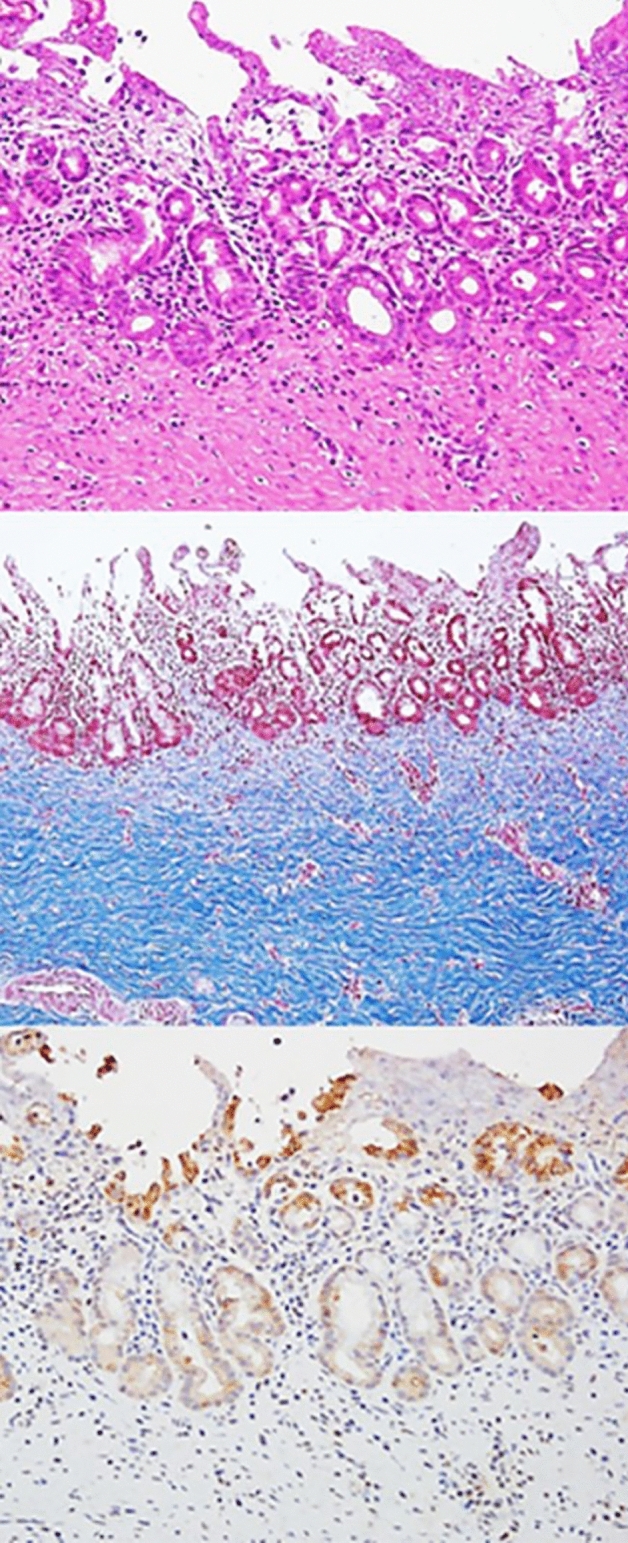

The common bile duct (CBD) diameter was 2.5 ± 0.5 mm in macroscopic findings. The biliary stricture length measured after harvesting of experimental animals was 36 mm ± 0.5 mm in macroscopic findings. Using H&E-stained tissue sections, the degree of histological damage was compared by examining the depth of inflammation, the degree of deposition of neutrophils, the presence of mucosal ulceration, and the overall score (Figs. 4, 5 and Tables 1, 2). The total histological score indicating histological damage of plastic stents was observed to be higher for the 3-month point than that for the 1-month point total score, median (range) of 1-month pigs vs. 3-month pigs: 6 (6–8) vs. 6.5 (6–8), although their difference was not statistically significant (p = 0.057) (Fig. 4 and Table 1). However, in the animal group in which the plastic stents were mounted for 5 months, the total score was observed to be significantly higher than those mounted for less time (total score, median (range) of 3-month pigs vs. 5-month pigs: 6.5 (6–8) vs. 9 (9–9), p = 0.029) (Fig. 5 and Table 2). The degree of tissue damage was compared using immunofluorescent staining (Fig. 6). From the top to the bottom, photomicrographs of H&E, Masson Trichrome staining, and immunofluorescence staining using CK 19 are shown. H&E staining revealed that the deposition degree of neutrophils of the tissue in the contact area of the plastic stents (Fig. 6). When the same area was observed after Masson Trichrome staining, extensive fibrosis of the tissue in the contact area was observed. At the bottom of Fig. 6, the immunofluorescent staining was performed using CK 19 for histologic evaluation.

In this study, we performed H&E staining, Masson Trichrome staining, and immunofluorescence staining (CK 19) to achieve an objective histopathological evaluation. Furthermore, the veterinarian pathologist in the animal laboratory evaluated and calculated the histological score based on the histological scoring system shown in Supplementary Table 1 commonly used in previous studies13–15. Histological damage caused by plastic stents was found to be higher when the follow-up time was longer. Interestingly, the total histologic score did not show any significant differences between different time points less than 3 months after inserting biliary plastic stents. However, at 5 months after stent insertion, a statistically significant difference in histological score was observed compared to that at shorter follow-up. Considering our results and cost effectiveness of the animal study, 1-month point after RFA seems to be the best timing for testing the new devices in the BBS in vivo swine models. Therefore, in clinical practice, it is recommended to remove the plastic stent between 3 and 6 months, which is the average patency period in previous studies16–18 to avoid histological damage.

Histopathological examination and evaluation

Pigs were euthanized at 1 month, 3 months, and 5 months after biliary plastic stents were inserted. Histopathological examination was then performed. After the liver, biliary tract, gallbladder, and duodenum were removed from experimental animals, a large amount of KCl (Potassium Chloride) was injected to induce euthanasia. From the extracted liver, biliary tract, gallbladder, duodenum, and AoV were dissected to the proximal end of the plastic stent located in the right and left intrahepatic bile duct. After the dissection, an incision was made in the longitudinal direction to confirm the proximal intrahepatic bile duct and distal biliary duct stenosis. The bile duct tissue was incised from the intrahepatic bile duct into which different plastic stents had been inserted and cut into sections, followed by H&E staining and Masson Trichrome staining. Histopathological examination was performed to reinforce the histological scoring method of previous studies. Scoring was performed in a blinded method using H&E-stained tissue sections. All sections were classified according to the extent of inflammation (1) (1, minimal; 2, confined to mucosa; and 3, extended to muscle with neutrophil infiltration). The severity of neutrophil infiltration was scored (2) as 0 for Absent, 1 for Mild, 2 for Moderate, and 3 for Severe. The presence of mucosal ulceration (3) was scored as 0 for Absent, 2 for Local, and 4 for Diffuse (Supplementary Table 1)13–15. Based on the histological scoring system shown in Supplementary Table 1, the histological score was calculated by a veterinarian pathologist in the animal laboratory of Samsung Life Sciences Research Institute.